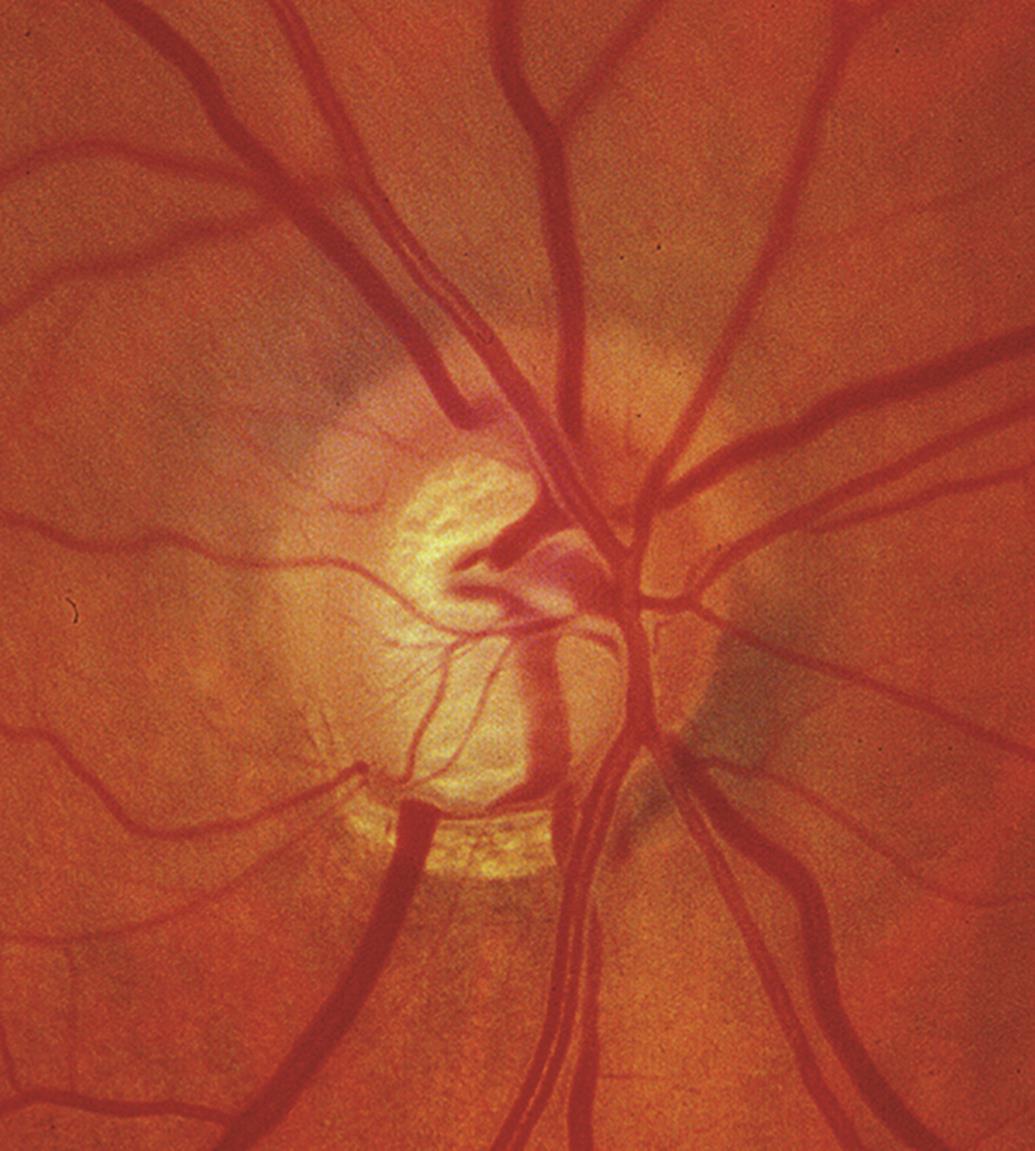

<후천성 시신경 유두오목 (Acquired Pit of the Optic Nerve, APON, Pseudopit)>

Pit 라는 것은 구멍 혹은 구덩이라고 하여, 크고 깊은 구덩이를 의미하는 용어입니다.

이는 시신경부위를 깊은 구덩이를 판것처럼 깊게 패인 부분이 발생하는 경우를 말합니다.

APON은 단순한 망막섬유층의 패임(notching)정도보다 더 깊게 패이는 것으로,

사상판에 도달할 정도와, 시신경유두의 가장자리에 닿을 정도로 국소적인 망막신경섬유층의 상실이 있음을 의미합니다.

즉, 사상판 위쪽에 존재해야하는 망막신경섬유층이 완전히 상실되면서,

사상판이 완전히 노출되는 것으로, 하얀게 사상판 조직을 직접 관찰할수 있습니다.